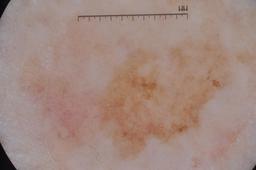

ISIC-DICM-17K (ISIC Dermoscopic Images and Clinical Metadata 17K) is a curated and balanced dataset derived from the International Skin Imaging Collaboration (ISIC) Archive Gallery. It comprises 17,060 dermoscopic images and clinical metadata (8,530 melanoma and 8,530 non-melanoma classes).

For more details, please follow the project’s GitHub repository: https://github.com/mmu-dermatology-research/isic-dicm-17k

This dataset was used in this study and benchmark to explore the effectiveness of multimodal learning for skin lesion classification:

S. Ahammed, X. Cui, W. Lu and M. H. Yap, "Skin Lesion Classification using Dermoscopic Images and Clinical Metadata: Insights from Multimodal Models," 2025 IEEE/CVF Conference on Computer Vision and Pattern Recognition Workshops (CVPRW), Nashville, TN, USA, 2025, pp. 222-230, DOI: 10.1109/CVPRW67362.2025.00027